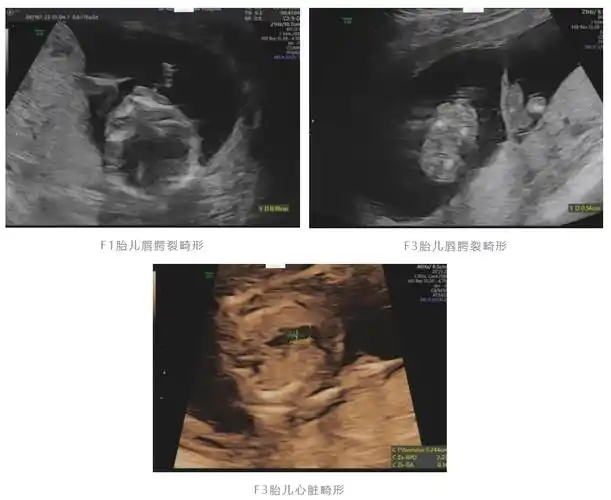

健康胎儿与畸形胎儿同卵双生!|邵逸夫_新浪财经_新浪网

同卵双胞胎,也称为单卵双胞胎,是由同一个受精卵分裂而成的,形成两个